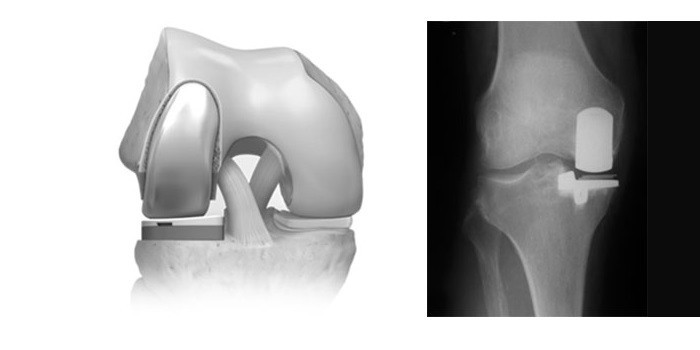

Коленные эндопротезы

Имплантаты подбирают по материалу, площади покрытия, углу сгибания, механизму крепления. Изготавливают их из полимеров, керамики или металла, при выборе проверяют на совместимость с организмом пациента. У материалов есть такие особенности:

Если имплантат покрывает всю поверхность сустава, он называется полным. Если он накладывается на 1 мыщелок или 2 поверхности из 3-х, то это частичный протез. По уровню мобильности выделяют 2 вида конструкций:

Одномыщелковое

Частичная замена сустава колена и хряща или полупротезирование выполняется, когда разрушен 1 мыщелок и сохранены функции связок.

Тотальное

Имплантат, который заменяет сустав полностью, изготавливают из металла, керамики или сплава, поэтому служит он долго. Замену проводят через 15-20 лет. Тотальное эндопротезирование коленного сустава выполняют при разрушении обоих мыщелков, тяжелых травмах, некрозе головки.